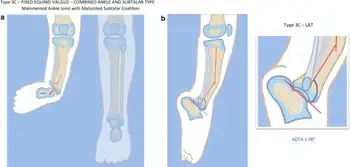

| a, b) Paley type 3c fibular hemimelia | |

- Absence of the lateral part of the ankle joint (due to absence of the distal end of the fibula), and what is left is unstable; the foot has an equinovalgus deformity

In terms of the diagnosis we find this is based on radiographic images and clinical exam[8]